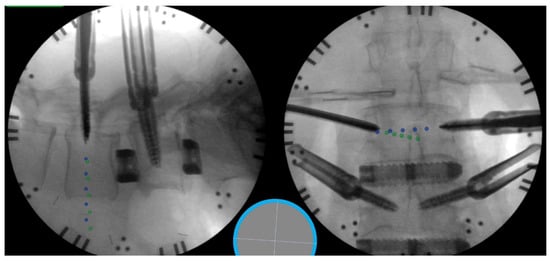

5.1. Fluoroscopic Navigation

5.2. Robotics

5.3. Novel Robotic Applications